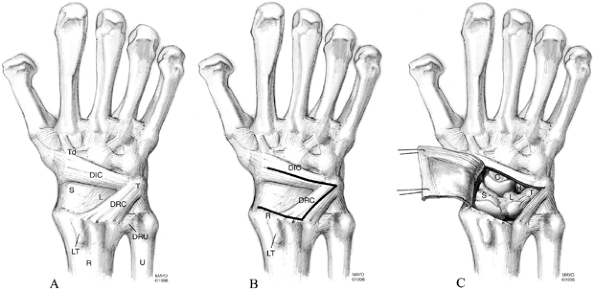

This approach is based on the anatomy of the dorsal radiocarpal and

dorsal intercarpal ligaments. The dorsal radiocarpal ligament attaches

to the dorsal rim of the radius between Lister’s tubercle and the

dorsal edge of the sigmoid notch, and distally to the dorsal lobe of

the triquetrum. At this same level, the dorsal intercarpal ligament

attaches to the triquetrum and spans the midcarpal joint to insert into

the dorsal surface of the

waist of the scaphoid, the lateral surface of the distal pole of the scaphoid, and the dorsal surface of the trapezoid.

Figure 41.6. A: The dorsal surface of the carpus defining the anatomy of the dorsal radiocarpal ligament (DRC) and the dorsal intercarpal ligament (DIC). (S, scaphoid; L, lunate; T, triquetrum; Td, trapezoid; DRU, distal radioulnar ligament; R, radius; U, ulna; LT, Lister’s tubercle). B:

The dorsal surface of the carpus outlining the landmarks used to create a fiber-splitting capsulotomy. The DRC attaches proximally along the dorsal rim of the radius between LT and the sigmoid notch and distally onto the dorsal lobe of the triquetrum. The DIC attaches ulnarly onto the dorsal lobe of the triquetrum and radially onto the scaphoid and trapezoid. The DRC is split by dividing the distance between LT and the sigmoid notch and connecting this point to the dorsal lobe of the triquetrum. The DIC is split by connecting the dorsal lobe of the triquetrum to the sulcus between the scaphoid and trapezoid. The capsulotomy can be reflected radially by incising the remaining attachment of the capsule along the dorsal rim of the radius to the tip of the radial styloid process. C: The completed fiber-splitting capsulotomy showing the reflected joint capsule. Exposed are the scaphoid, lunate, hamate, and capitate, as well as the radial two-thirds of the radiocarpal joint and the entire midcarpal joint. (From Berger RA, Bishop AT. A Fiber-splitting Capsulotomy Technique for Dorsal Exposure of the Wrist. Tech Hand Upper Extremity Surg 1997;1:2, with permission.) |